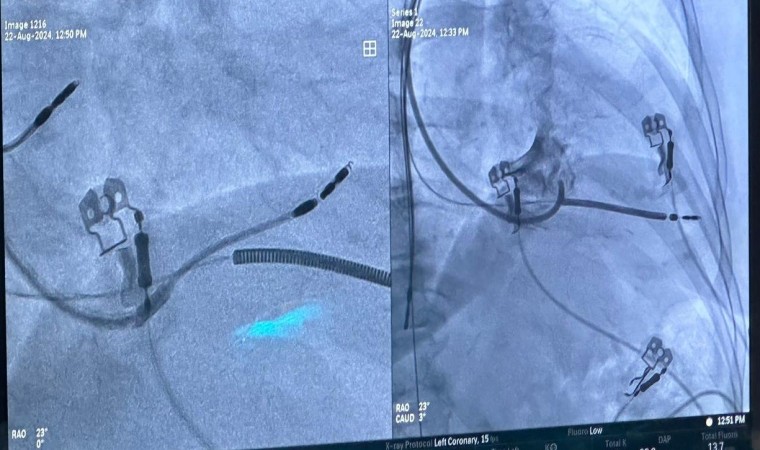

Elazığ Fethi Sekin Şehir Hastanesi’nde Kardiyoloji Uzman Dr. Öğretim Üyesi Zeki Çetinkaya ve Kardiyoloji Uzmanı Mehmet Ali Gelen tarafından ilk defa ‘Sol Dal Pacing’ sistemi ile kalp pili ameliyatı yapıldı.

Elazığ Fethi Sekin Şehir Hastanesi, sağlık alanında ki başarılı çalışmalara bir yenisi daha ekledi. Türkiye’de sadece belirli merkezlerde yapılan ‘Sol Dal Pacing’ ameliyatı Fethi Sekin Şehir Hastanesi’nde 3 hastanın ameliyat edilmesiyle başladı. Hastanede görevli Kardiyoloji Uzmanları Dr. Öğretim Üyesi Zeki Çetinkaya ve Uzm. Dr. Mehmet Ali Gelen, aldıkları eğitimin ardından hastanede ‘Sol Dal Pacing’ yöntemi ile kapalı pil ameliyatını başarılı bir şekilde gerçekleştirdi. Kalbin içerisindeki çarpıntıların tespit edilmesi ve ardından ablasyon ile teknik tedavi uygulanan ameliyat yöntemi, daha önceden yapılan kalp ameliyatlarının nefes darlığı ve kalp yetmezliği oluşturmasını ortadan kaldırıyor. Başarılı ameliyatların ardından bilgiler veren doktorlar, dünyada yeni uygulanan Türkiye’de ise belirli merkezlerde yapılan ameliyat yöntemi ile Fethi Sekin Şehir Hastanesi’nin bu alanda öncü olacağını belirtti.

Türkiye’de belirli merkezlerde yapılan fakat Elazığ’da bir ilki gerçekleştirdiklerini aktaran Dr. Öğretim Üyesi Zeki Çetinkaya, “Sol Dal Pacing yöntemi ile 3 hastamızı ameliyat ettik. Bundan sonra da bu şekilde devam edeceğiz. Bu ameliyatın özelliği kalbin doğal ileti sistemi üzerine pil kablosunu yerleştirdikten sonra kalbin sağ ve sol karıncıklarının uyumlu şekilde çalışmasını sağlıyoruz. Diğer normal taktığımız pillerde ise öncelikle kalbin sağ karıncık kısmı uyarılıyor, sonra sol karıncık kısmı geç uyarılıyordu. Bu şekilde 10 hastanın 2’sinde kalp yetmezliği ve nefes darlığı olabiliyordu. Bu pil yöntemi, dünyada yeni uygulanıyor. Hastalarımız bu ameliyat yöntemi ile daha fayda görmektedir. Özellikle ritim bozukluğu ve nefes darlığı olan hastalarda bu işlemleri başarılı şekilde uygulamaktayız. Bu ameliyat, Ankara, İstanbul ve belirli merkezlerde yapılmaktadır. Burada ise ilk defa yaptık ve başarılı olduk. Katkılarından dolayı Prof. Dr. Uğur Canpolat hocamıza da teşekkür ederiz. Buranın ilerleyen dönemlerde bölge merkezi olma ihtimali de çok yüksek. Bu ameliyatın özelliği doğal ileti sistemi üzerine kablo koyularak kalbin senkron şeklinde yani iki ventürkülün de aynı anda kasılmasını sağlıyoruz. Bu şekilde hastalarda nefes darlığı daha az oluyor. Bu pil yöntemi takıldığında hastalarımız daha konforlu ve nefes darlığı olmayacak şekilde yaşamlarını devam ettirebilirler” dedi.

Kardiyoloji Uzmanı Dr. Mehmet Ali Gelen ise “Normalde kalp yetersizliği ve ritim bozukluğu olan hastalarımızda kalp pili, sık tercih edilen bir yöntemdir. Özellikle dünyada yeni yapılan ve Türkiye’de bazı merkezler de yapılan bu yeni yöntemi bizde Elazığ’a kazandırmak istedik ve 3 hastamızın ameliyatlarını başarılı bir şekilde gerçekleştirdik. Özellikle kalbin ana ileti sistemine pacing yaparak bir pil ablasyonu yapıldı. Bu hastalarda kalp yetersizliğini riskini azaltır ve yaşam konforunu arttırır. Aynı zamanda hastaların ilaç tedavisi yanıtını da arttırabilen bir yöntemdir. Önceden hastalar, bu tarz özellikli işlemleri yaptırmak için Ankara, İstanbul, İzmir ve Bursa gibi şehirlere gitmeleri gerekiyordu fakat biz bu sol dal pacing ameliyatını başarılı bir şekilde yaptık. Bundan sonra bölge ve Elazığ’da ki tüm hastalar, farklı bir şehre gitmeye gerek duymadan Fethi Sekin Şehir Hastanesi’nde ameliyatlarını olabilecekler” ifadelerini kullandı.